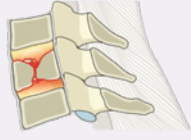

A fratura tipo A1 corresponde à fratura por impactação, são lesões raras que resultam de forças de compressão axial em flexão, o disco intervertebral é comprimido levando ao acunhamento do corpo vertebral, o que geralmente ocorre ao longo da placa terminal superior. Por definição é uma fratura que poupa o muro posterior da vérebra. Pelo fato de o córtex posterior do corpo estar intacto, e como comumente não há lesão do complexo ligamentar posterior (CLP), o risco de lesão neurológica é baixo. No entanto, danos ao CLP podem ocorrer em fraturas do tipo A1 criando uma lesão instável, a associação com alargamento do espaço interespinhoso, subluxação e perda de lordose cervical indica uma provável ruptura ligamentar, a chamada lesão por flexão oculta.